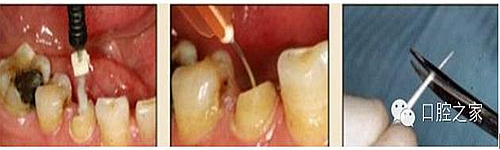

圖3:根管內(nèi)殘留物

圖4:超聲去除根管殘留物。

根管壁殘留物的存在直接影響著纖維樁的粘接和固位,是纖維樁脫落的主要原因之一。由于圓形的根管鉆和根管形態(tài)不完全一致,終鉆預(yù)備完成后大多情況下樁道側(cè)壁會有不同程度的牙膠和封閉劑等殘留物附著(圖 3)。因此,建議X線檢查根管預(yù)備情況,選用超聲潔牙機更換較細工作尖進入根管,徹底去除樁道根管壁上附著的殘留物(圖4)。使用根管銼去除殘留物時,很難清除干凈;禁止使用牙膠溶劑如丁克除、氯仿等有機溶劑去除殘留物,以免破壞根尖區(qū)牙膠的封閉,或有機溶劑粘附于根管壁形成蠟?zāi)ざ绊懻辰印?#pages##